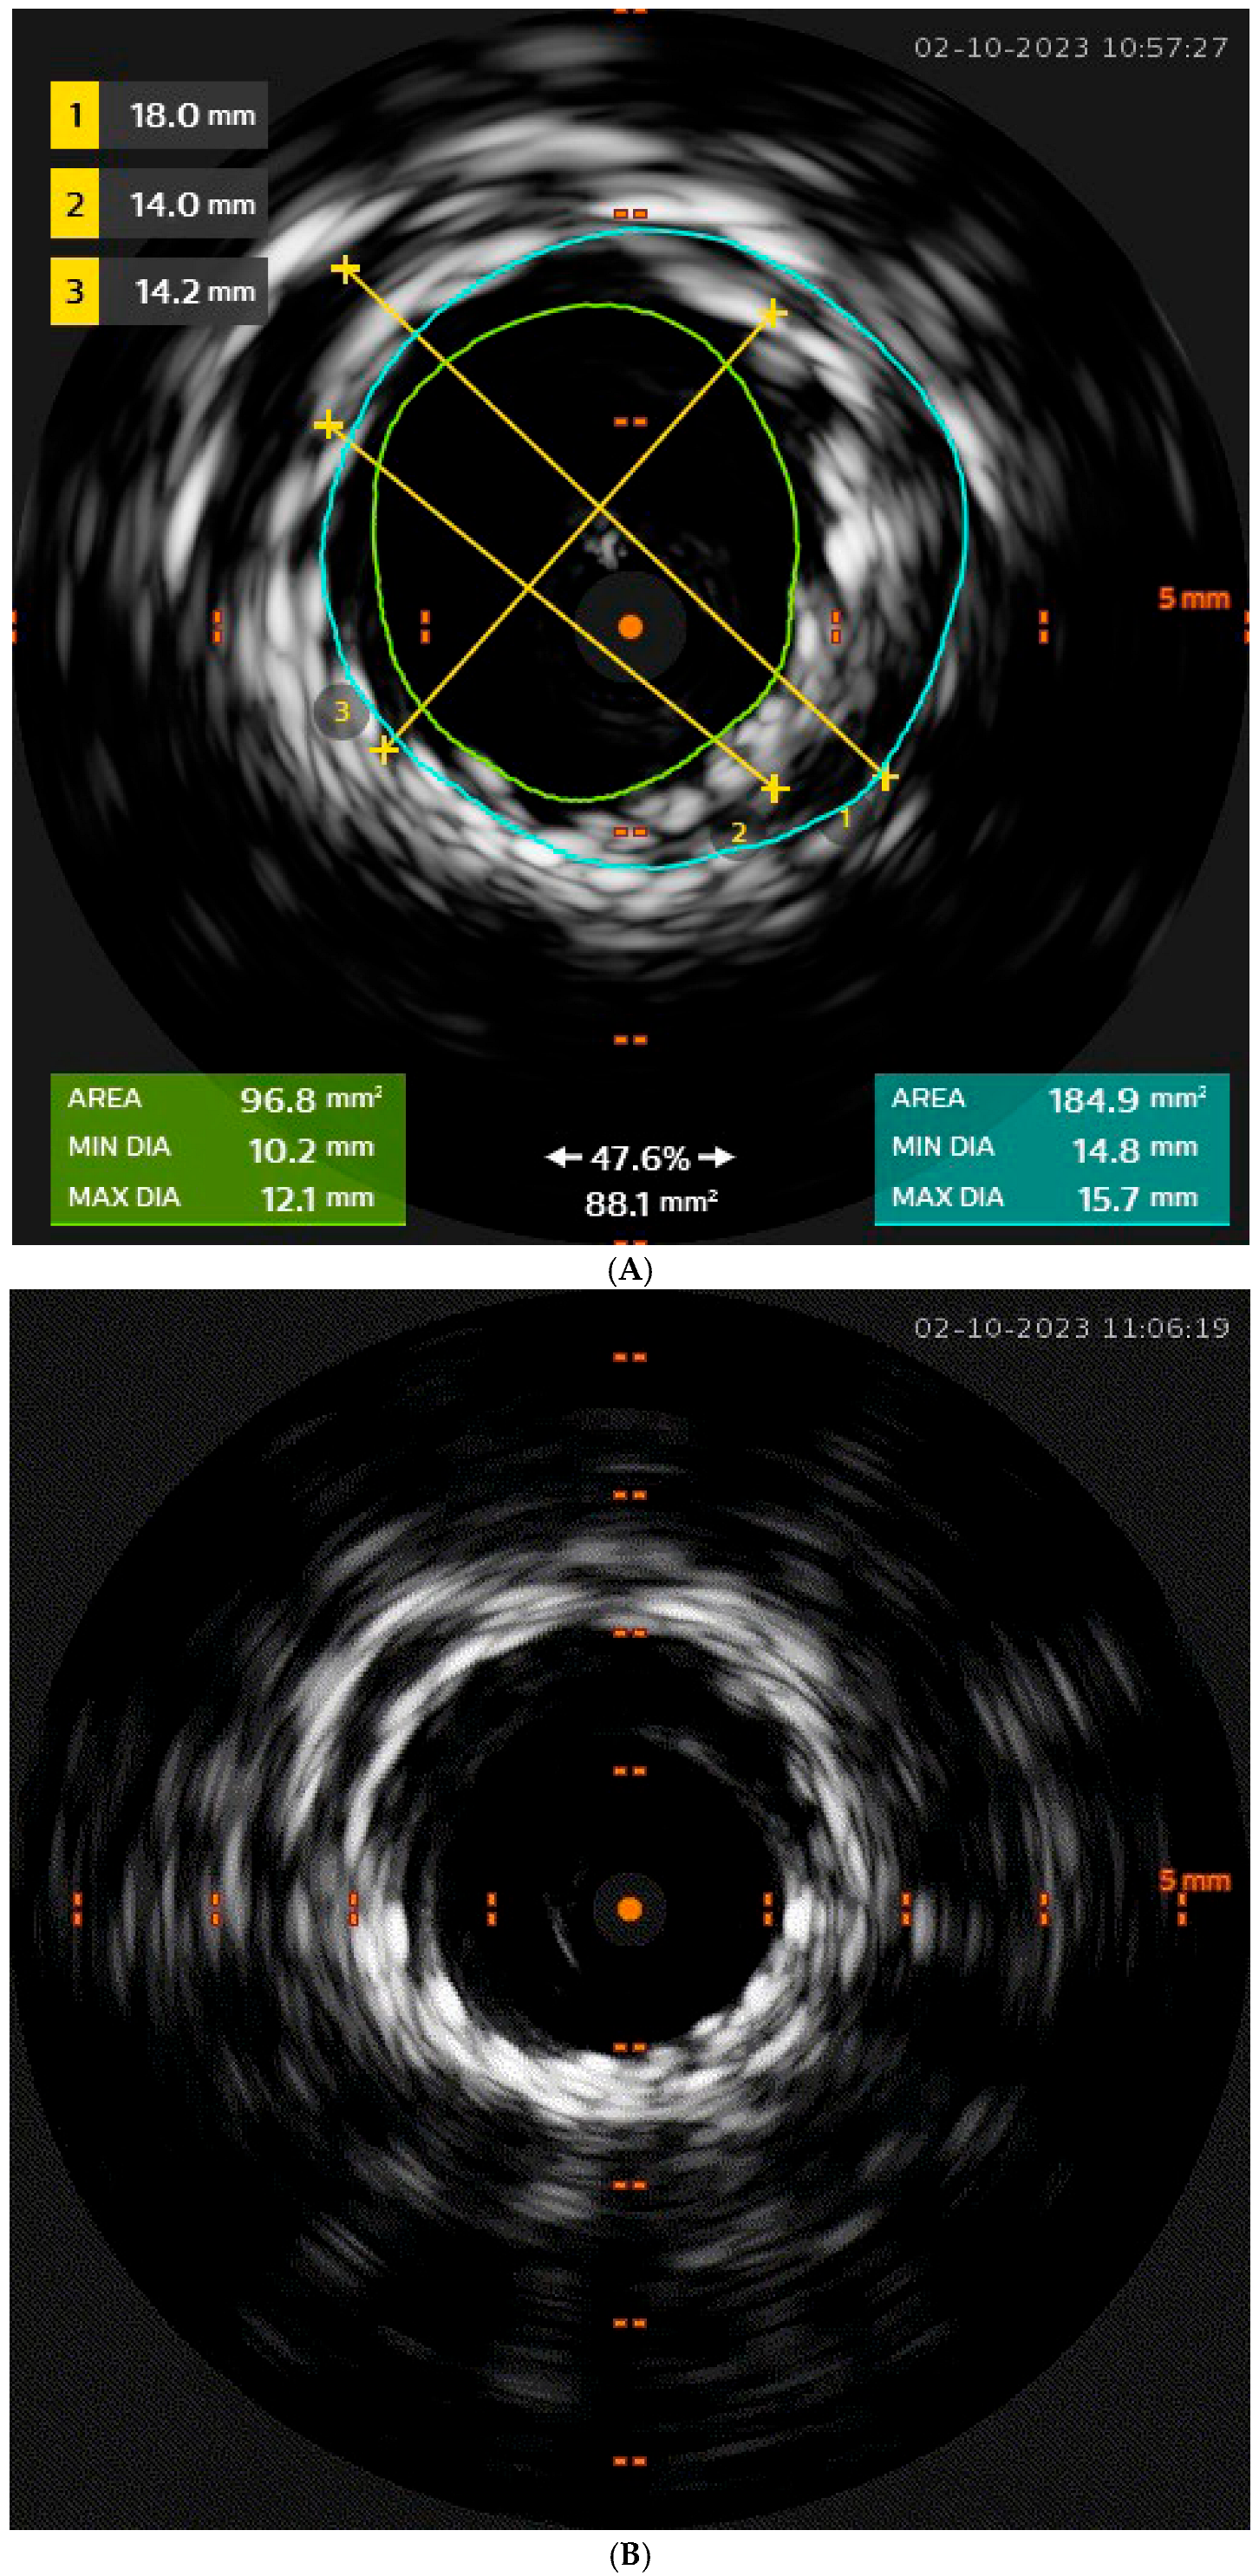

4.1. Infrarenal EVAR